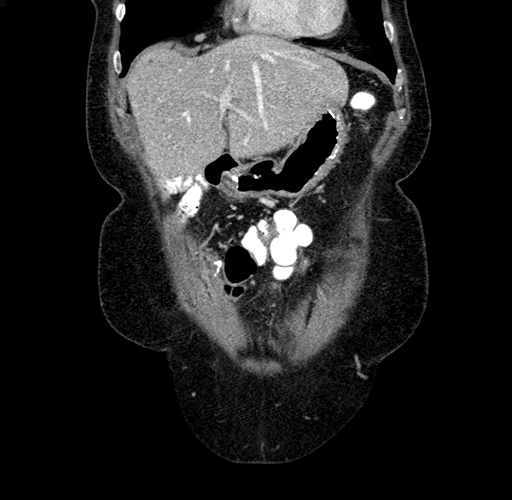

Pre-Chemo: Coronal Venous

Coronal Venous